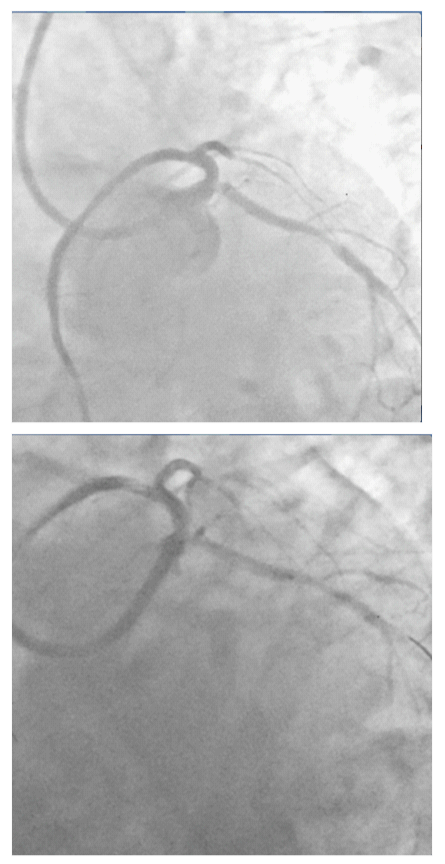

The patient was wheeled into the catch lab after pre-loading with 60mg Prasugrel and 300mg of Aspirin. He received 7,500units of unfractionated heparin and underwent coronary angiography from the right femoral route, which revealed 70% distal left main (LM) stenosis, and 70-80% ostial blocks of the left anterior descending (LAD) and left circumflex (LCX) arteries (Figures 2 & 3), (Video 1).The right coronary artery had a 50% stenosis at mid level (Figure 4). The patient was continuing to have chest pain despite prior administration of intra-venous morphine in the ER. He however was in a position to give informed consent for primary percutaneous intervention (PCI) subsequent to explaining that PCI would be a viable alternative keeping in view the urgency of intervention in his condition.

Figure 3 Spider view showing tight distal left main, ostial left anterior descending and ostial left circumflex arteries stenosis.